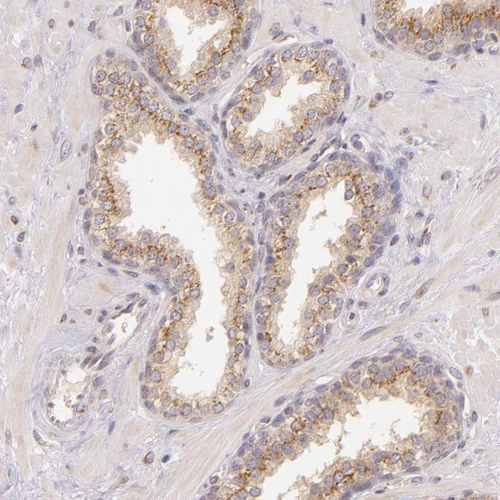

Immunohistochemical staining of human placenta shows strong granular cytoplasmic positivity in trophoblastic cells.